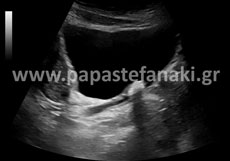

Υπέρηχοι άνω κάτω κοιλίας

H προετοιμασία του ασθενούς. Πρέπει να είστε νηστικός-ή τουλάχιστον έξι ώρες πριν την εξέταση.

Είναι καλό από την προηγουμένη μέρα να αποφύγετε τροφές με κυτταρίνη, όπως χόρτα, όσπρια, λαχανικά και φρούτα, καθώς και γαλακτοκομικά (γάλα, γιαούρτι). Ελεύθερα κρέας, ψάρι, κοτόπουλο, ζυμαρικά.

Δεν πρέπει να έχει προηγηθεί την ίδια ημέρα γαστροσκόπηση, ορθοσκόπηση, εξέταση στομάχου ή εντέρου.

Επίσης θα πρέπει 2 ώρες πριν την εξέταση να πιείτε 5-6 ποτήρια υγρών (νερό, χυμό μη ανθρακούχο κλπ) ώστε να γεμίσει η ουροδόχος κύστη (άρα δεν πρέπει να ουρήσετε πριν την εξέταση).